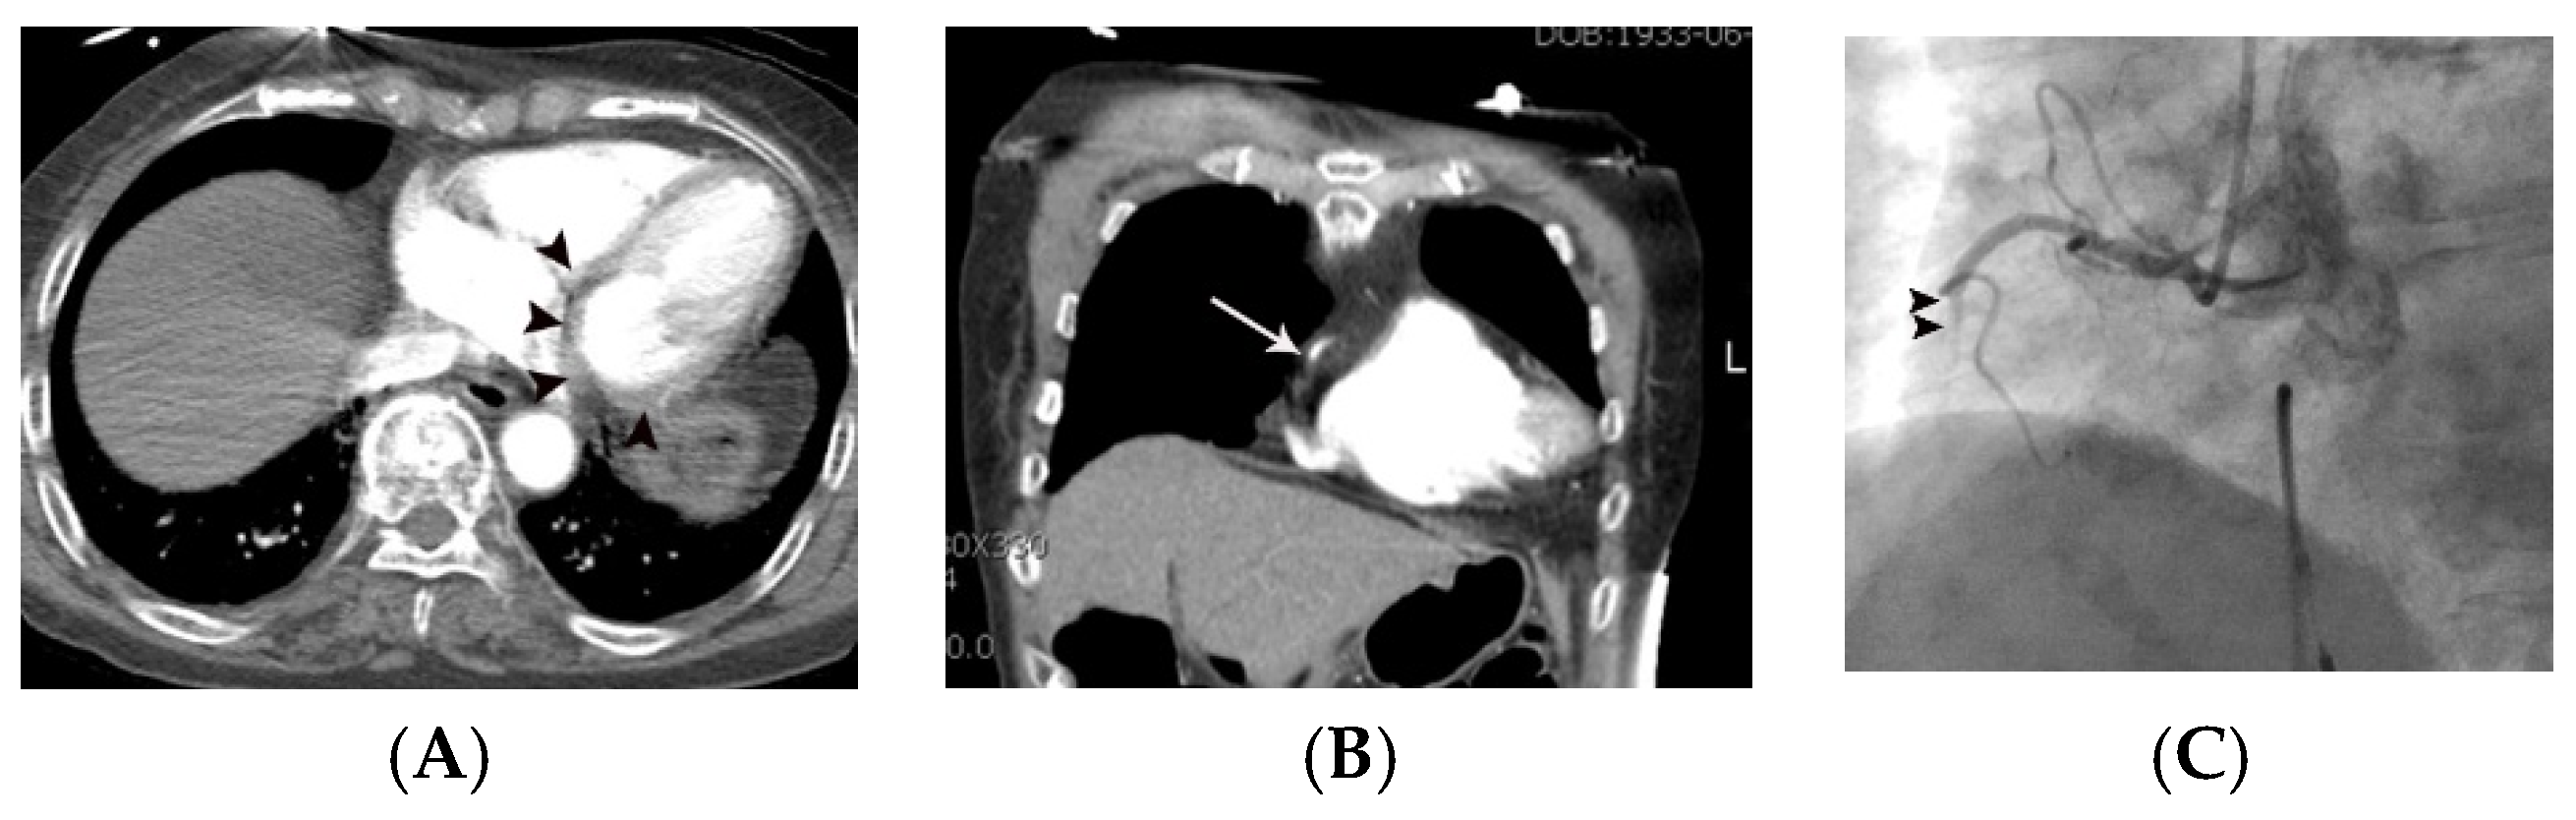

Figure 2.

Coronary artery occlusion in the mid-right coronary artery demonstrated on non-gated enhanced chest CT in a 67-year-old woman with acute myocardial infarction. (A) Artifact vs. true myocardial perfusion defect (arrowheads) was noted in the inferior wall of the left ventricle on an axial image. Suspicion of acute myocardial infarction was not described in the initial radiologic report. (B) On retrospective analysis of the coronary arteries, an abrupt cut-off (arrow) of contrast was noted in the mid-right coronary artery on a coronal reformatted image. Note that only minimal motion artifact is present in this image, even though the image was obtained without ECG gating. (C) Subsequent emergent coronary angiography confirmed the non-gated chest CT finding (arrowheads).